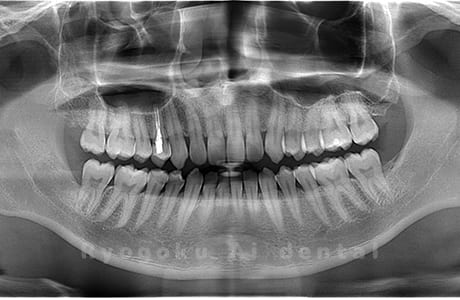

Case02

- 原因

- 下顎の水平埋伏智歯

- 治療内容

- 下顎の水平埋伏智歯を抜歯

<リスク・副作用>

手術後は痛み、腫れ、痺れなどの副作用が生じる場合があります。